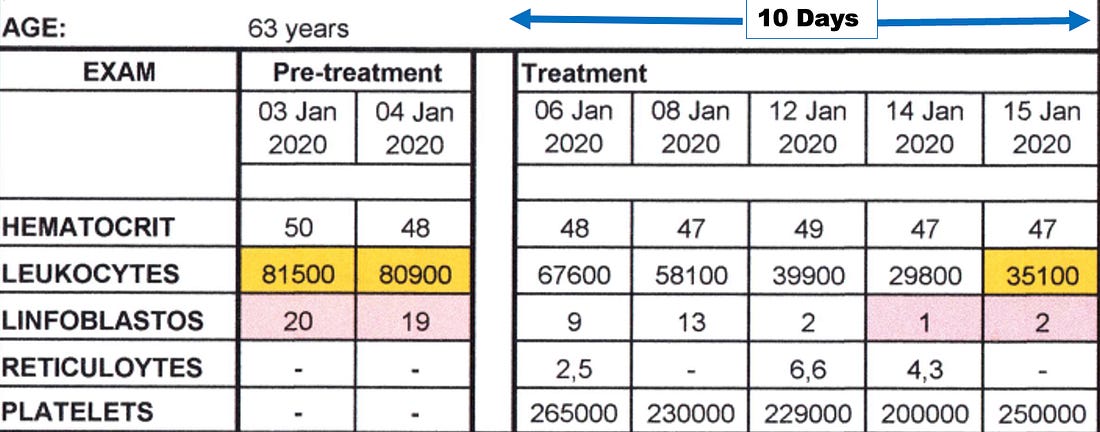

advice). •He felt very strongly about the necessity of chelation therapy in cancer (e.g., to prevent subsequent heart attacks following successful D-hematoxylin treatments—which occurred years later in some of Tucker’s cases) and to that you should not give leukemia patients with anemia iron as the cancer needed that to grow (to the point he would sometimes also chelate iron in leukemic patients). •McCann was also very focused on cultivating bacteria on a target media that would dissolve specific biological targets (e.g., he cultured bacteria from a dead cow’s cataract and then found it could eliminate other cataracts; likewise, he found this approach worked for cancer). Note: my experience with individuals like McCann is that some of their insights are spot on while others they have a deep conviction in are ultimately not correct. The Next PhaseLike many alternative therapies, D-hematoxylin grew up in “the Wild West” of alternative medicine. This was made possible by its very low toxicity profile, which allowed it to be used in humans at widely varying doses without significant side effects. Fortunately, the threads keeping D-hematoxylin from being lost eventually converged in Ecuador with a doctor who’d successfully treated 44 out of 45 cases of microbiologically confirmed chronic bacterial prostatitis using DMSO combined with antibiotics that were applied directly into the bladder (much in the same DMSO is FDA approved to treat interstitial cystitis) who then tested negative for any infection 15-20 days following treatment (with no subsequent recurrences), demonstrating DMSO's ability to counteract bacterial resistance. Note: interestingly, Stanley Jacob, was still alive when these treatments were initiated (he died in 2019 at age 91). At the start of the prostatitis treatments, the doctor in Ecuador contacted him for advice, and Jacob encouraged the experiment, agreeing it was a good idea, even though he hadn't heard of anyone attempting it before. As he’d heard of McCann through Ecuador’s medical community, these prostatitis successes inspired that doctor to try intravesical DMSO mixed with hematoxylin for a prostate cancer patient (which was administered in the same manner and frequency as his prostatitis treatments). This worked, and he gradually began using it for other prostate cancer patients and then other cancers as well, which gradually grew into a fifteen-year research project on the therapy (which he's shared with me over the course of a few months). Note: I also know of one individual who used D-hematoxylin intrarectally over a prolonged period to locally treat a cancer there, but the data on this approach is still limited. Recent D-Hematoxylin PatientsThat

project involved treating approximately 85 patients, with the cure rate

in patients who had not previously received chemotherapy averaging

between 80-90%. As such D-hematoxylin is an excellent cancer treatment

but it is not perfect and will not work for everyone. •Leukemias (particularly acute leukemia) Note: myeloproliferative neoplasms (e.g., polycythemia vera, essential thrombocythemia and primary myelofibrosis) depend upon a mutant protein for survival which was shown to be susceptible to disruption by a few small compounds including hematoxylin. While D-hematoxylin has not been tested on these disorders, this study (along with the other known effects of DMSO and D-hematoxylin) suggest it could be an effective treatment for them. The cancers with a poorer response included: •“Solid” tumors Additionally, if there is a cancer marker associated with the tumor (e.g., CEA or PSA), it will often rapidly drop, making it very easy to track the progress of D-hematoxylin. As the following cases show, many of the improvements were quite profound: •A 54-year-old female patient with Classic Hodgkin Lymphoma which had invaded 72% of her bone marrow, with CD20-positive expression. She had a variety of symptoms (e.g., recurrent pleural effusions and anemia), but since her religion did not permit blood transfusions, she received only D-hematoxylin and EDTA and then had a full recovery (with no recurrence in twelve years of follow up). The most striking aspect of this case was the change in her bone marrow biopsy, after three months of treatment with D-hematoxylin (unlike chemotherapy) it selectively destroyed the cancerous cells, allowing normal ones to regrow and rapidly addressed her anemia. •A 72 year old patient with leukemia who was anemic and had her anemia rapidly improve following D-hematoxylin: Likewise, similar bone marrow changes were seen in her. Note: another similar leukemic patient on D-hematoxylin with anemia had no improvement. After investigating, it was determined this was due to her regularly using WD40 on a daily basis (without respiratory protection) and hence having a bone marrow intoxication which was directly damaging the bone marrow (and in turn the leukemia diagnosis may have been incorrect). •A 16 year old male with a mediastinal seminoma that received 16 D-hematoxylin infusions, 5 IV vitamin C infusions and then one chemotherapy session (on July 7) where cisplatin and bleomycin were combined with DMSO (after which he continued chemotherapy and has recovered from the cancer). •A 63-year-old male with cholangiocarcinoma (a rare, aggressive and notoriously difficult to treat cancer of the bile duct) who received D-hematoxylin plus chelation and vitamin C (but no chemotherapy). During his successful treatment, a drain from his bile duct was also monitored for tumor markers. Additionally, the cancer debris could be seen in the drainage tube (an internal-external percutaneous transhepatic biliary drainage catheter)—something which the Ecuador doctors now view as essential to have if D-hematoxylin will be used in this cancer: Note: another bile duct cancer patient (a 68 year old female) received palliative D-hematoxylin while waiting for surgery and chemotherapy (which ultimately could not be done because of how advanced the cancer was). Her cancer markers levels significantly improved following D-hematoxylin (and continued to reduce during gaps in treatment), but she eventually lost the will to live and passed after 16 months. •A 63-year-old man with B-cell lymphoproliferative disorder who received D-hematoxylin for 10 days (with no other treatment), experienced a significant drop (normalization) of his white blood cell count during that time then stopped at the advice of his hematologists, and two years later died from COVID. •A man who had a stable bladder polyp which became cancerous following a covid vaccination (with the initial sign being a large blood clot in the urine) which when examined had spread in a large portion of the urinary tract’s endothelium. It was surgically removed, but due to how far it had spread, the urologist told the patient he would only survive for two months. They then began five weeks of intravesical and IV D-hematoxylin, and in four years, the cancer never returned (which led to the urologist telling everyone about the “amazing” surgical procedure they had performed). •A 55-year-old female who had a mediastinal tumor (type unknown as it was wrapped 560° around the aorta and hence could not be biopsied) which fully resolved after 33 daily D-hematoxylin treatments. Additionally, this was the CT prior to treatment where the tumor can be seen around the aorta: While this was the CT two weeks following the D-hematoxylin treatment: Lastly, at five years follow up, there was no recurrence. •A 27-year-old female with acute lymphoblastic leukemia reacted poorly to two sessions of chemo, was classified as terminal, and then was started on D-hematoxylin. She had a significant improvement in her cancer and simultaneous improvement in her anemia which continued long after conventional treatments for anemia were halted (which did not include blood transfusions as she was a Jehovah’s Witness). In a before (1-2-2020) and after (2-1-2020) video I saw of this patient, she initially looked very frail and had difficulty walking, while just a month later (after 31 days of treatment), she had no difficulty walking and looked vibrant and robust. Additionally, they continued to monitor her on a monthly basis, and four years later, she’d had a healthy baby, and had her hematocrit range from 42 to 48 (which is slightly above average) indicating she had no further risk of anemia (even though hematologists in the hospital had predicted her reckless pregnancy would cause severe anemia). Additionally, her ESR (which had been significantly elevated prior to treatment) normalized (and remains normal 5 years later). Lessons from EcuadorIn addition to observing a remarkable degree of success from D-hematoxylin, the Ecuadorian team was able to discern a variety of patterns (many of which mirrored Tucker’s previous observations) that helped craft their treatment protocols. For example: •While DMSO alone can somewhat help with cancer, the effects of DMSO combined with hematoxylin are completely different from what would be observed with DMSO alone. •They saw many signs during their treatment protocols that D-hematoxylin selectively targeted cancer cells. •Cancers did not develop resistance to D-hematoxylin (which is a common challenge with many chemotherapies). •While some tumors rapidly disappear, other types frequently become avascular (which stops their growth) and dried-out, blanched, or fibrous rather than being directly shrunk (e.g., I reviewed cases where a brain cancer simply stopped growing). In many cases, those tumors are then very easy to extract surgically. Note: to my knowledge, everyone besides that Ecuadorian team who treats with D-hematoxylin still uses Tucker’s protocol and has not tried to improve upon it. Variations in D-Hematoxylin EfficacyOn